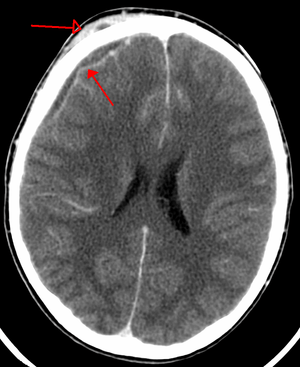

| An abscess that has led to an intracranial subdural empyema as seen on CT | |

Subdural empyaema is a form of empyema in the subdural space.

Bacterial or occasionally fungal infection of the skull bones or air sinuses can spread to the subdural space, producing a subdural empyema. The underlying arachnoid and subarachnoid spaces are usually unaffected, but a large subdural empyema may produce a mass effect. Further, a thrombophlebitis may develop in the bridging veins that cross the subdural space, resulting in venous occlusion and infarction of the brain. With treatment, including surgical drainage, resolution of the empyema occurs from the dural side, and, if it is complete, a thickened dura may be the only residual finding. Symptoms include those referable to the source of the infection. In addition, most patients are febrile, with headache and neck stiffness, and, if untreated, may develop focal neurologic signs, lethargy, and coma. The CSF profile is similar to that seen in brain abscesses, because both are parameningeal infectious processes. If diagnosis and treatment are prompt, complete recovery is usual.